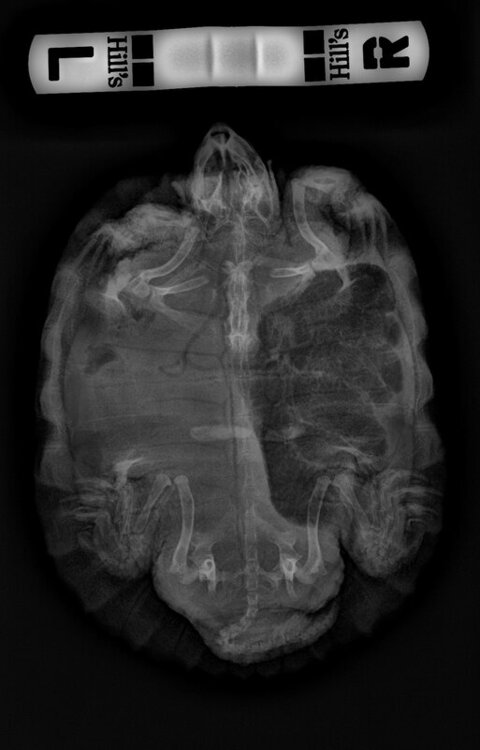

2) Красноухая черепаха

Увидел крен на бок,  обратились к герпетологу, сделали рентген, поставили диагноз - Ателектаз правого легкого.

В общем, черепаха первые дни после курса была активной, потом стала вялой и очень плохо ела. Сделали позавчера повторный снимок, объем легкого еще меньше стал.

Врач сказал , что легкое уже не спасти и нужно наблюдать за динамикой. По ощущениям стало еще хуже, постоянно на берегу сидит и глаза не открывает, кладу его в воду на 5 мин каждый день, он даже там глаза не открывает. Подскажите,  что еще можно сделать, чтобы помочь моей черепашке, и какие шансы на то, что он будет жить.

ПОСЛЕ.jpg

ДО.PNG